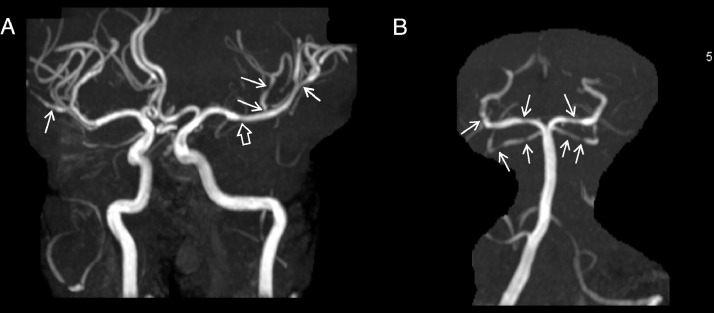

He received normal saline bolus, morphine, and divalproex sodium, which improved his pain to 5/10. Magnetic resonance imaging (MRI) brain revealed a focal acute infarct in the right cerebellar hemisphere and focal cortical edema along the right frontal convexity (Fig. 1). MR angiogram demonstrated multifocal segmental arterial narrowing involving the posterior cerebral arteries and superior cerebellar arteries, as well as the middle cerebral arteries (Fig. 2).

Fig. 2.

MR angiogram. Multifocal segmental narrowing in the bilateral M2 middle cerebral artery branches (A, arrows) and left M1 segment (A, open arrow) and in the posterior cerebral arteries and superior cerebellar arteries (B, arrows).